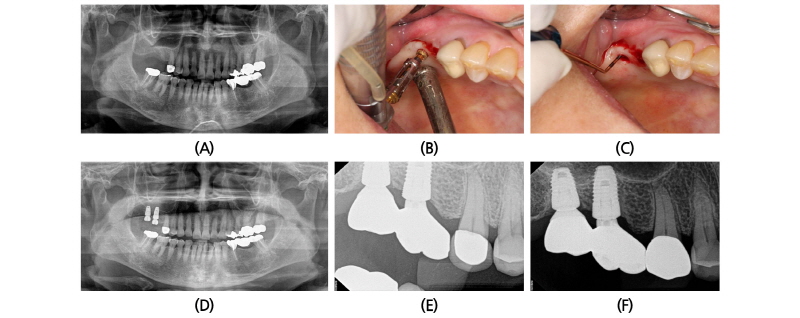

50세 남자 환자가 상악 좌측 제 2 대구치의 치주질환으로 발치 후 자가 치아를 이식하였으나 골 흡수 및 동요도가 발생되어 발치 후 임플란트를 식립하기로 계획하였다. 발치된 치아는 이식재로 활용하기 위해 자가치아뼈이식재(Korea Tooth Bank, Seoul, Korea) 처리를 의뢰하였다. 방사선 사진상 식립 예정 부위의 잔존 치조골 높이는 약 7 mm 정도로 계측되었다. 치조정 절개를 가하여 골점막 피판을 거상하고 계획된 깊이까지 골을 삭제한 후 상악동점막 거상을 위해 baloon을 삽입하였다. 약 5 ml의 식염수를 주입하여 조심스럽게 점막을 거상시켰다. 점막 천공이 발생되지 않은 것을 확인한 후 준비된 자가치아뼈이식재를 충천하였다. 이후 직경 6.0 mm, 길이 8 mm의 임플란트(Dentium Superline, Suwon, Korea)를 식립하였다. 식립 직후 Ostell mentor (Ostell AB, Sweden)를 사용해 측정한 ISQ값은 37을 나타내었다. 임플란트 주변 치조정 결손부에도 자가치아뼈이식재를 이식하고 창상을 봉합하였다. 식립 2주 후에 봉합사를 제거하였고 5개월 후 2차 수술을 시행한 후 치유 지대주를 연결하였으며 이때 측정된 ISQ 값은 70이었다. 식립 6개월 후 최종 보철물이 성공적으로 장착되었고 식립 26개월 후 방사선 사진에서 안정적으로 임플란트가 유지되고 있었다(Fig. 1).